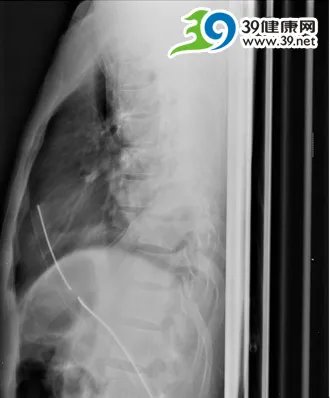

当武警广东省总队医院的专家们第一次听取病情汇报时,也不禁倒抽了一口冷气。伤者的整个胸椎被强大的冲击力硬生生的挤成了“S”形状,胸7.8椎体完全脱位,部分椎体甚至已经相互重叠,部分肋骨体外可见,复位极其困难,风险极大。

当主刀医生,武警医院骨科陈少文主任打开小李的胸腔时,完全被里面的创伤惊呆了。正常人的胸廓具有固定和保护功能,保护内部重要器官如心、肺等,但是伤者的胸廓已经完全被破坏,摇摇晃晃,已经失去了支撑和保护功能,部分肋骨甚至往后翻插出去。